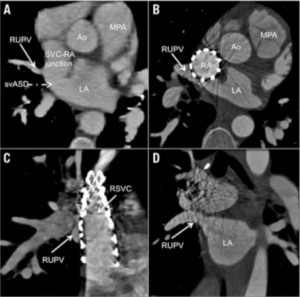

疾患としては図の通り上大静脈下端付近に欠損孔が存在し、後方に存在する左心房との交通を認めます。経過は二次孔欠損型とほぼ同様ですが、洞不全症候群や上室性頻脈の割合が高いなどの特徴があります。病態的な治療適応は二次孔欠損型と同様で右心負荷や血栓症既往などが挙げられます。一方、形態的にはカテーテル治療の適応は慎重な判断が必要です。右房の後方にある右肺静脈部や右肺静脈―左心房接合部付近が、欠損孔になることがほとんどであるため、ステント留置後の右肺静脈圧排、閉塞に注意が必要です。当施設ではMRIによる血行動態評価、経食道エコー、造影CTによる形態評価を行い、さらにCT画像を元に3Dプリンターで疾患モデルを作成し3次元的にステント留置が可能かを評価しています(図2, 図3)。

平均年歴53歳(38-66歳)の5症例に対して治療を施行し、全例で手技に成功し、手技合併症も認めませんでした。また平均8.1ヵ月の観察期間で、全例に運動耐容能の改善が得られています。さらに論文報告の後、現在までに20症例近くの治療が施行され、全例が治療に成功しています。また、手技合併症は心房中隔穿刺の合併症によるタンポナーデ症例1例のみで、同症例もドレナージで改善しており重篤な合併症は認めておりません。全例6ヶ月後にCTで経過フォローを行い、現在までステント脱落や損傷は認めません(図6)。